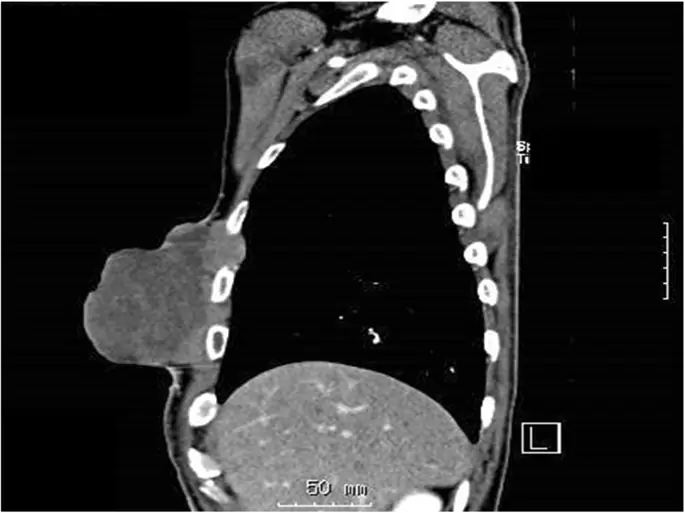

Компьютерная томография (КТ) показала массивную массу размером 10 см × 7 см × 9 см (рис. 2). Метастатических поражений не наблюдалось. Патологическими диагнозами образцов, резецированных в предыдущей больнице, были плеоморфная саркома правой молочной железы и атерома левой молочной железы, что согласуется с недифференцированной плеоморфной саркомой (рис. 3).

фигура 2

Сагиттальная компьютерная томография, показывающая опухоль, выступающую из стенки грудной клетки. Опухоль также проникает в межреберную область

Изображение в полном размере